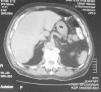

Se realizó biopsia cutánea frontal derecha que objetivó importante hiperplasia sebácea, sin otras alteraciones (fig. 2). Se solicitó analítica rutinaria añadiendo C1q inhibidor, hormonas tiroideas, autoinmunidad, marcadores tumorales, ácido vanilmandélico, catecolaminas y 5 hidroxi-indolacético (5-HIA) en orina de 24h. En los resultados destacó una discreta anemia, velocidad de sedimentación globular 70 y 5-HIA en orina muy elevado (339mg/24h con un control de 1–8,2mg/24h). En la radiografía de tórax se apreció una imagen residual parahiliar derecha, que permanecía estable respecto a controles previos. En la tomografía axial computarizada toraco-abdominal se puso de manifiesto la presencia de metástasis hepáticas no visibles en la que se realizó 8 meses antes (fig. 3). En el Servicio de Otorrinolaringología se diagnosticó una hipoacusia de conducción por edema de ambos conductos auditivos externos. En Oftalmología se objetivó una disminución del campo visual por engrosamiento palpebral. La serie ósea realizada fue normal.